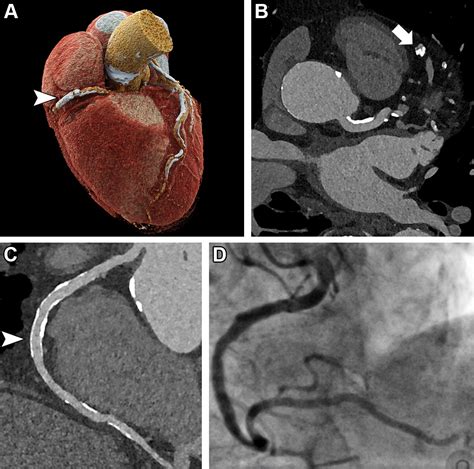

At its core, a Cardiac CT scan is an imaging test that allows cardiologists and radiologists to see if your coronary arteries are narrowed or blocked by plaque buildup—a condition known as atherosclerosis. Unlike traditional stress tests, which provide functional information about how your heart handles exertion, a cardiac CT provides anatomical information. It captures images of the heart while it is beating, using sophisticated gating technology to synchronize the image acquisition with your heart rhythm.

This technology is particularly effective at identifying early-stage heart disease before symptoms manifest. By visualizing the calcified and non-calcified plaque within the arterial walls, physicians can initiate preventative treatments far earlier than previously possible.

Once the scan is complete, the images are sent to a radiologist or a specialized cardiologist who analyzes the anatomy of your coronary arteries. They will look for the presence and extent of plaque, the degree of arterial narrowing (stenosis), and the presence of any calcium deposits. You will receive a formal report, and your primary doctor will discuss the findings with you to determine the next steps in your care plan. Depending on the findings, these steps may include lifestyle modifications, cholesterol-lowering medication, or further diagnostic testing.